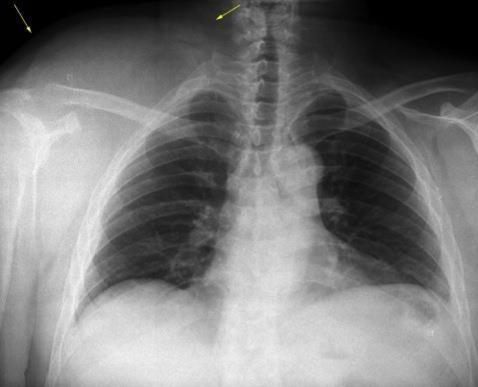

Masa axilar izquierda y derrame pleural derecho. Implantes pleurales, paraespinales . Ganglios en mamaria interna. Linfoma B difuso

Jaffe ES. Diagnosis and Classification of Lymphoma: Impact of Technical Advances.

2005. Masa pulmonar.

Linfoma NH de cél. B. Invasión Transtorácica.

Afectación axilar